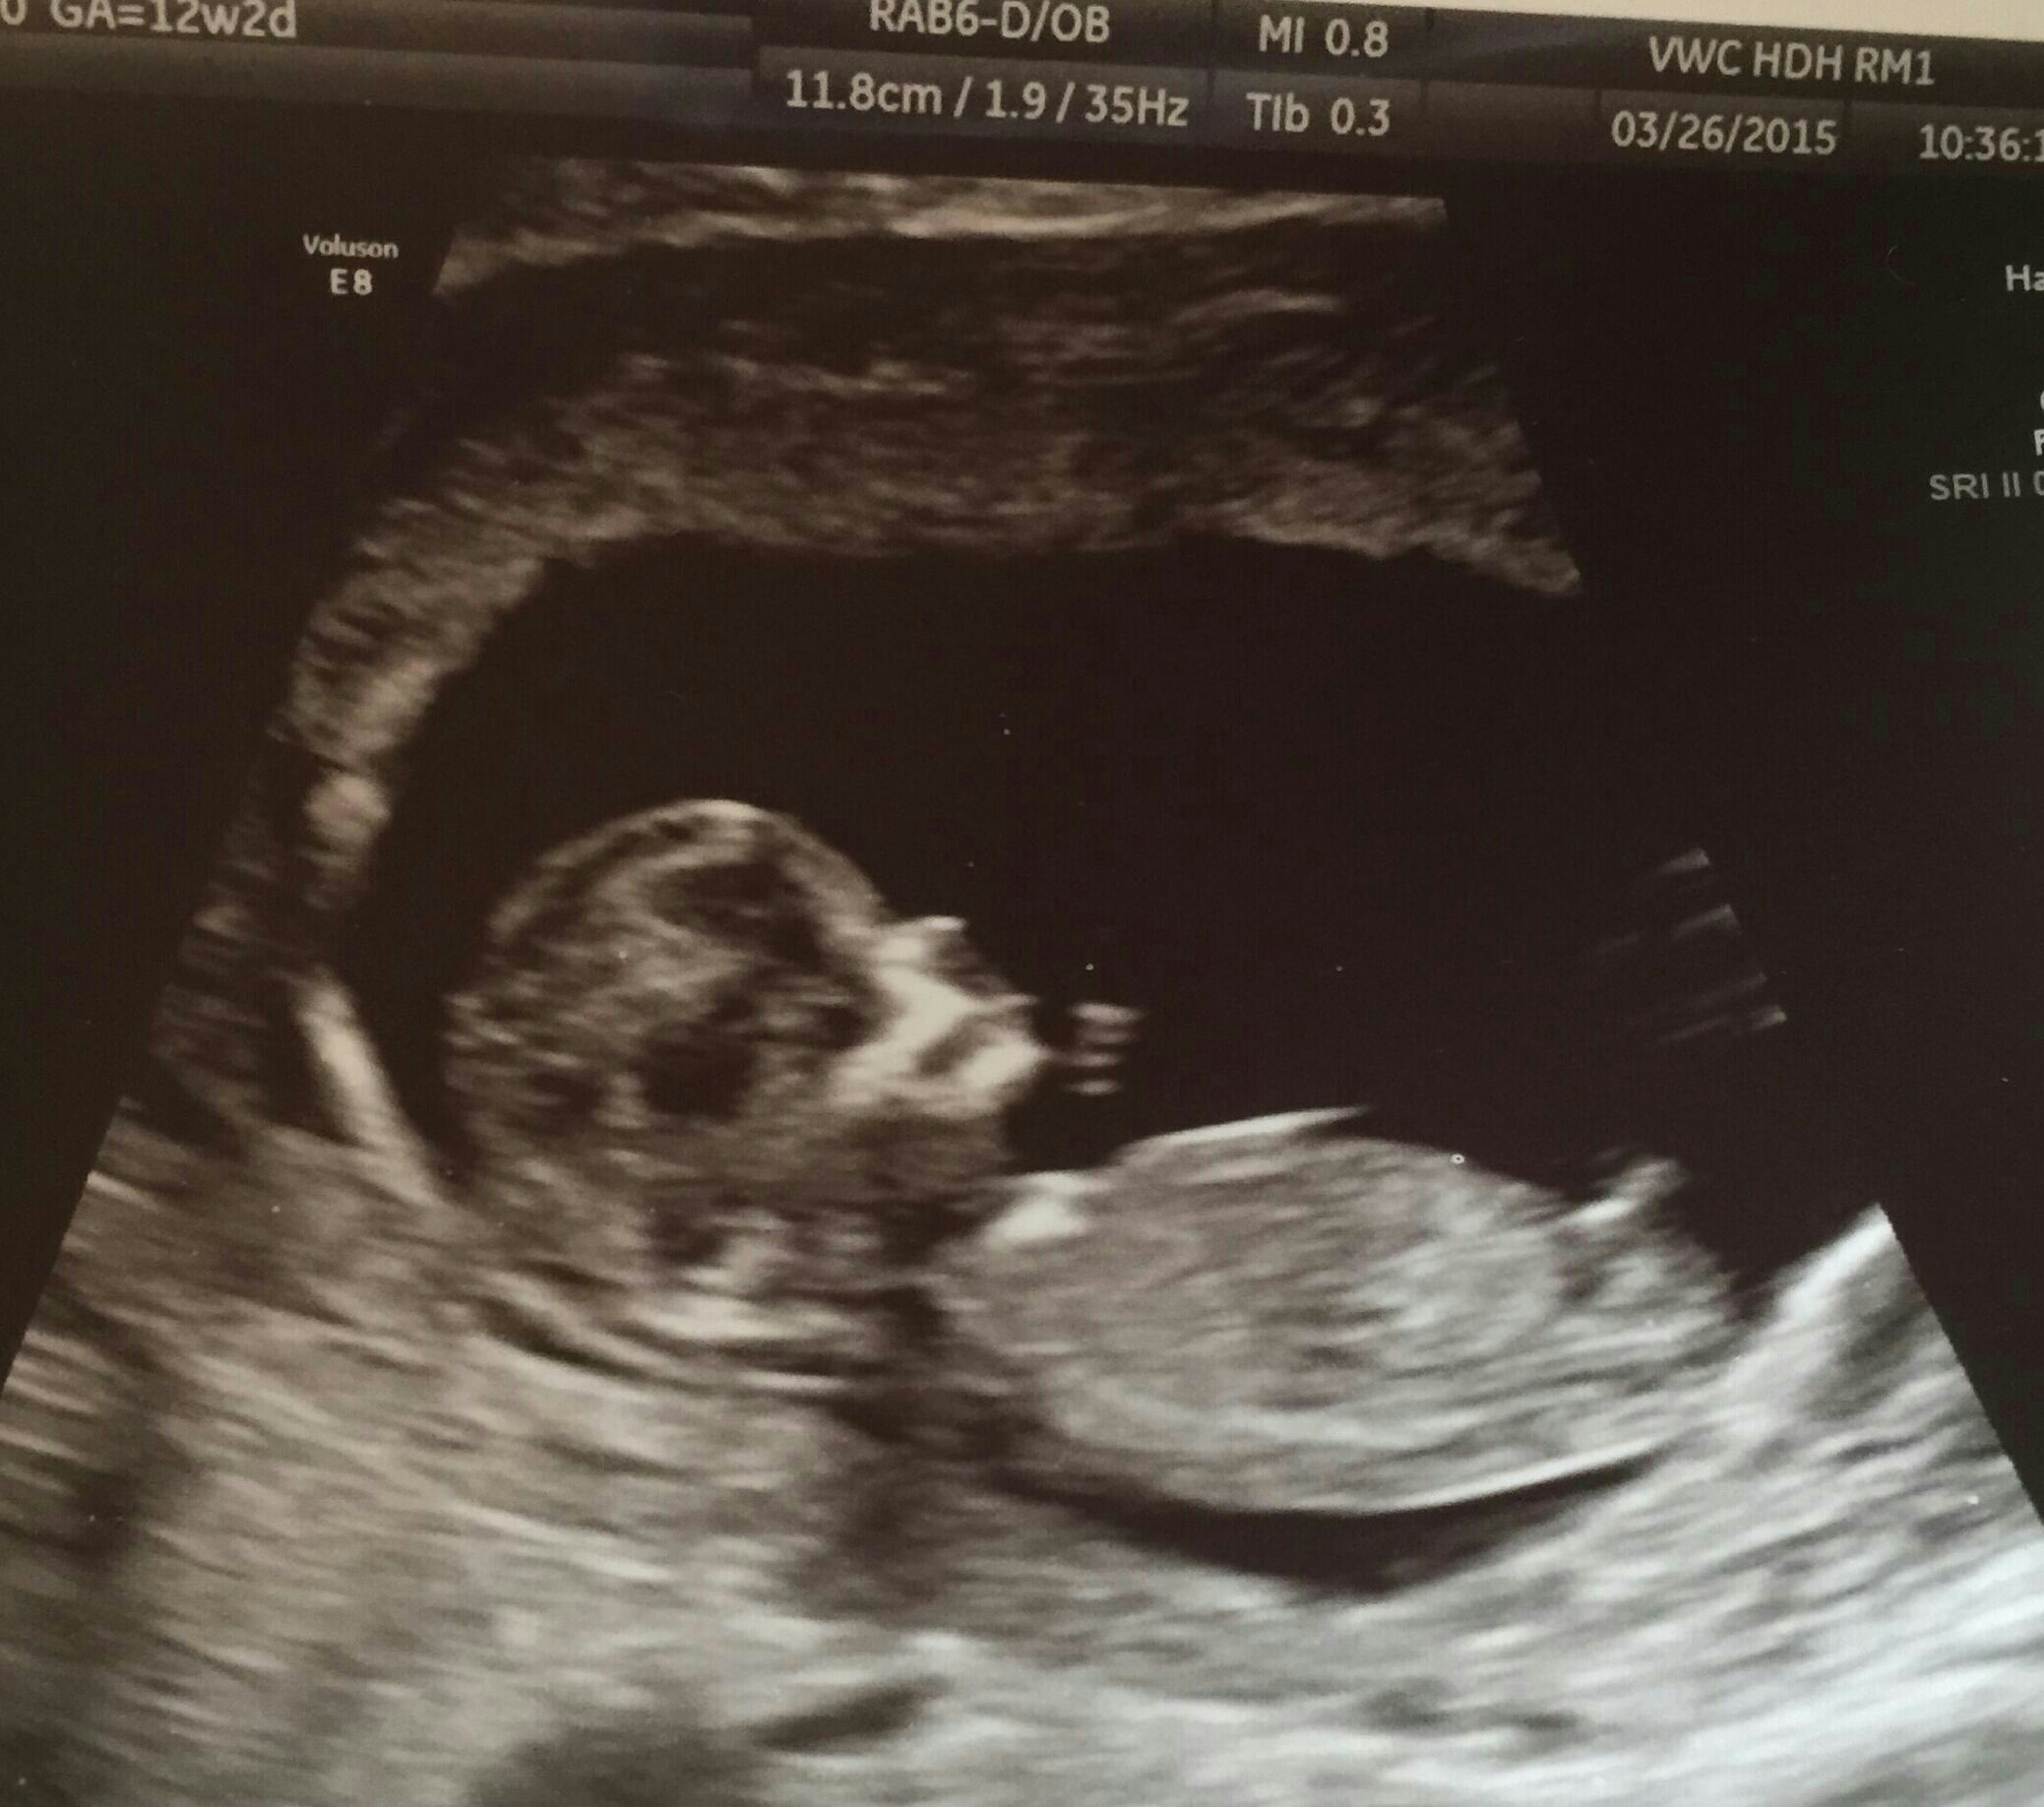

Is this a nub or part of the leg??...

If you think its a nub...Any gender guesses??

Measured 12wks and 3 days.

Thinking boy

Leaning boy

Boy!!!

It's not a leg. Boy.

Yes boy nub!

boy nub!! Legs dont bend that way